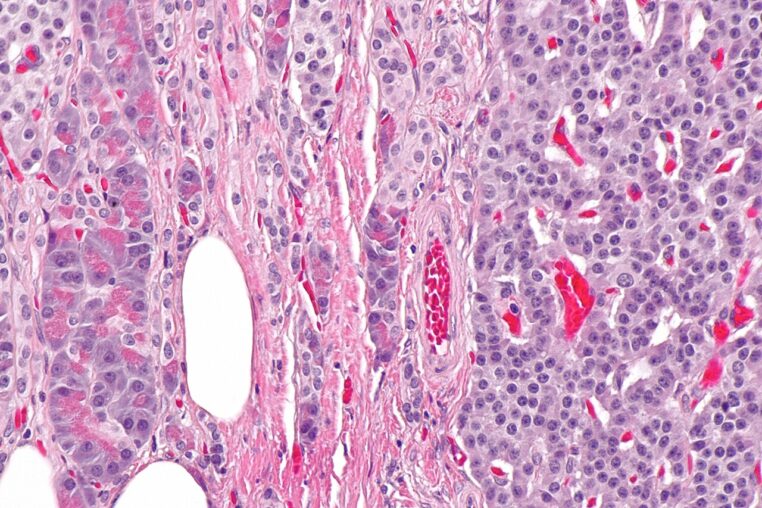

Longtemps classés parmi les cancers rares. Les cancers neuroendocriniens (ou néoplasmes neuroendocriniens) sont en réalité un ensemble de tumeurs très hétérogènes. Ils naissent à partir de cellules dites « neuroendocrines », à cheval entre système nerveux et système hormonal. Capables de produire des messagers chimiques. On les retrouve surtout dans le tube digestif, le pancréas et les poumons. Mais ils peuvent apparaître presque partout dans l’organisme.

On parle souvent, pour simplifier, de deux grandes catégories. D’un côté, les tumeurs neuroendocrines (TNE/NET), souvent plus lentes, parfois « silencieuses » pendant longtemps. De l’autre, les carcinomes neuroendocriniens (CNE/NEC), plus agressifs et à croissance rapide, qui exigent une prise en charge urgente.

Or, même cette distinction ne suffit pas à décrire la complexité des cas. Le site d’information de NCUK et les documents de réseaux spécialisés comme UKINETS rappellent que ces cancers regroupent des formes multiples. Comme on peut en trouver pour le cancer colorectal, des localisations variées. Et des trajectoires très différentes, ce qui complique la vigilance en médecine générale.